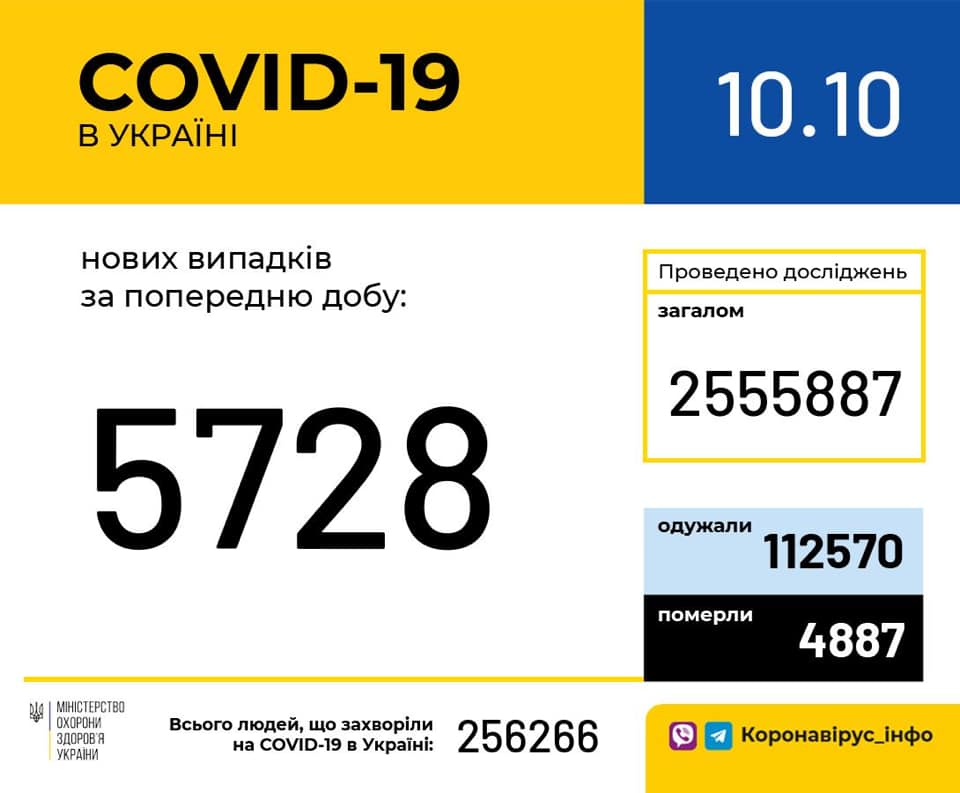

Більше 3 тисяч випадків захворювання на коронавірус зафіксували в Україні за добу

11.09.2020 09:37